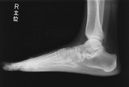

• レントゲン撮影

1-2.

レントゲン撮影で画像診断をします。